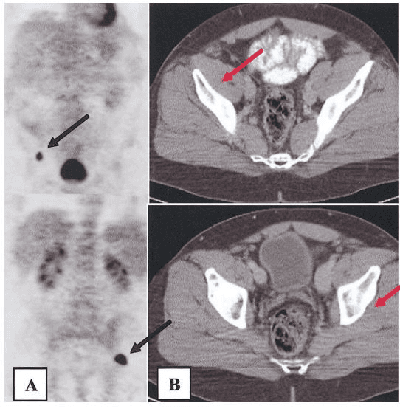

Abstract:The application of machine learning to radiological images is an increasingly active research area that is expected to grow in the next five to ten years. Recent advances in machine learning have the potential to recognize and classify complex patterns from different radiological imaging modalities such as x-rays, computed tomography, magnetic resonance imaging and positron emission tomography imaging. In many applications, machine learning based systems have shown comparable performance to human decision-making. The applications of machine learning are the key ingredients of future clinical decision making and monitoring systems. This review covers the fundamental concepts behind various machine learning techniques and their applications in several radiological imaging areas, such as medical image segmentation, brain function studies and neurological disease diagnosis, as well as computer-aided systems, image registration, and content-based image retrieval systems. Synchronistically, we will briefly discuss current challenges and future directions regarding the application of machine learning in radiological imaging. By giving insight on how take advantage of machine learning powered applications, we expect that clinicians can prevent and diagnose diseases more accurately and efficiently.